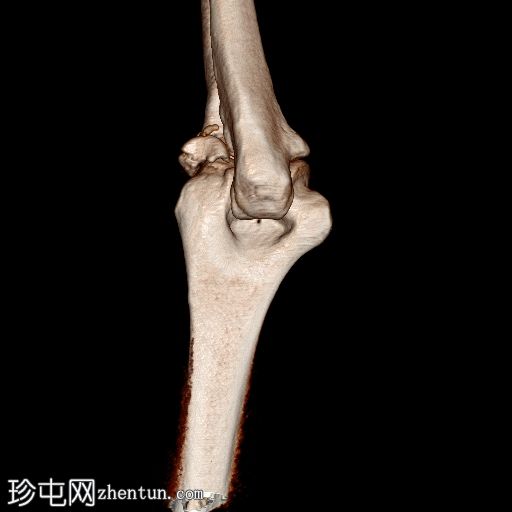

3D平扫

显示整个桡骨头粉碎性骨折,特征为两个以上大骨折块,以及倾斜且受压的关节节。

这表明该骨折为不稳定骨折,根据Mason桡骨头骨折分型,为IIIC型。

远端肱骨和可见尺骨未见骨折征象。

对于 Mason IIIc 型骨折,如本例,需要切开复位内固定 (ORIF)。